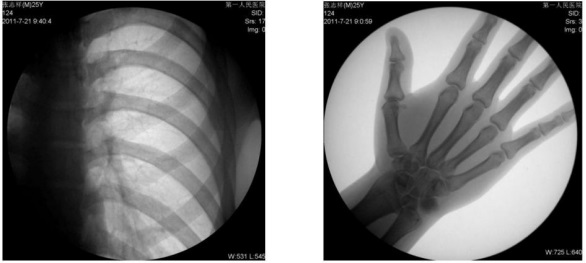

1) 胸部檢查:能實(shí)現(xiàn)全胸透視動態(tài)觀察,對于需要在透視下動態(tài)觀察的病變,如肺部腫瘤、氣管異物等可進(jìn)行實(shí)時點(diǎn)片。胸部透視是體檢中的常規(guī)檢查項(xiàng)目,臨床意義在于檢查有無肺癌, 特別是早期肺癌。使用胃腸機(jī)可通過胸部透視雙肺,縱膈有無病變,以確定病變部位的部位、大小、密度,與周邊組織關(guān)系,常見的疾病,如肺炎、肺結(jié)核等。胃腸機(jī)可以從各種角度動態(tài)詳細(xì)觀察肺、心臟或其他胸部的病變,對病變的情況可以有個比較全面地了解。

平板數(shù)字胃腸機(jī)臨床影像